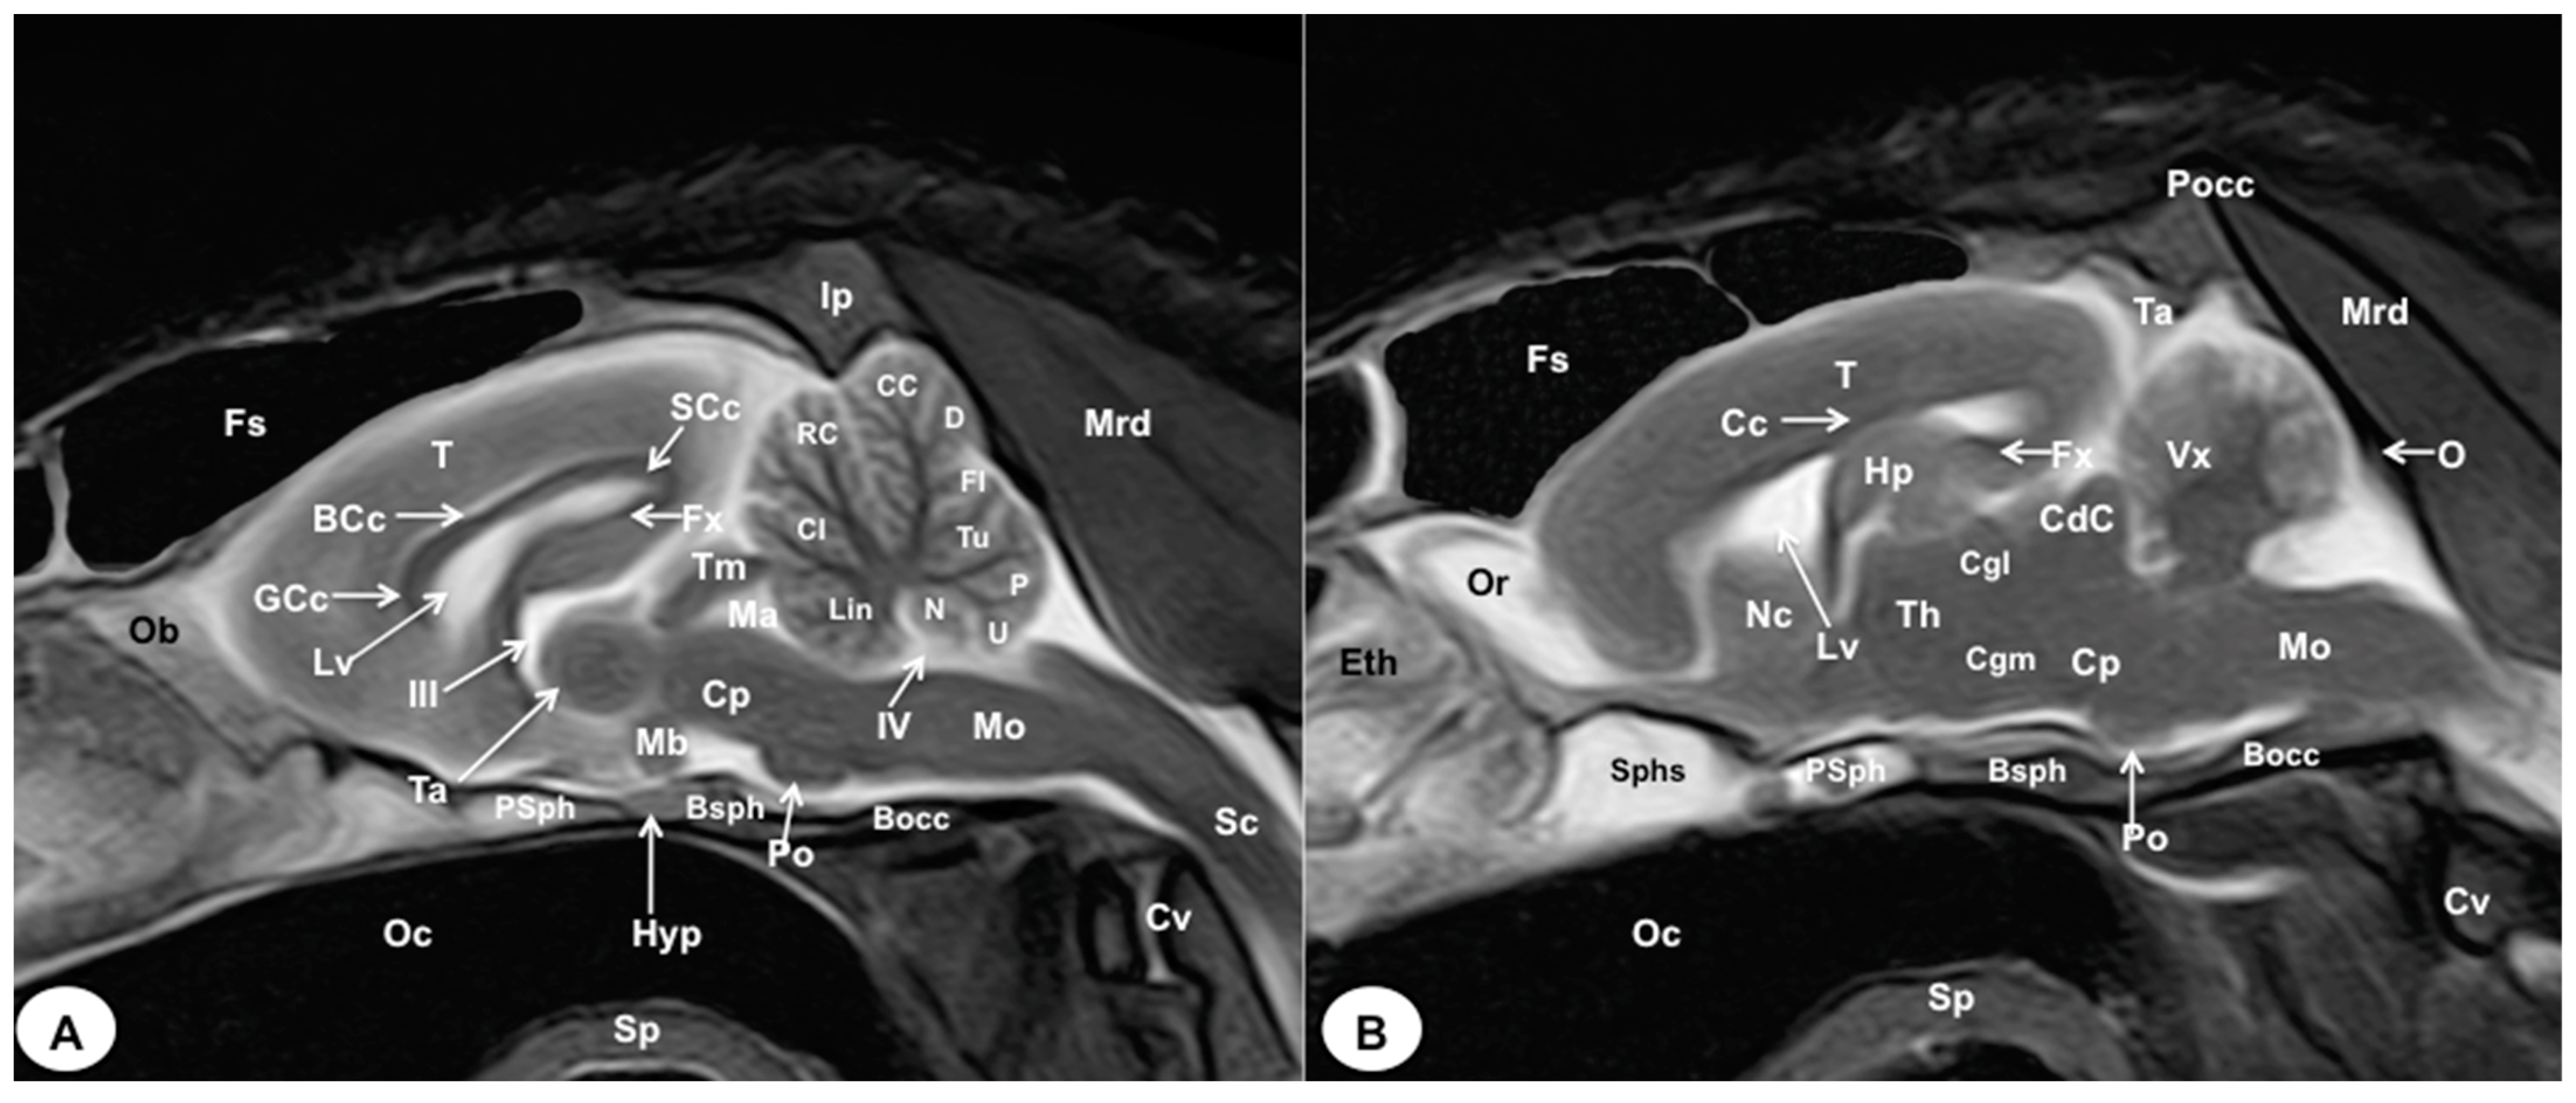

Figure 8.

Sagittal (A) and parasagittal (B) T2W MR images of the crested porcupine head. Fs: frontal sinuses; Ip: interparietal bone; Pocc: Protuberantia occipitalis externa; Eth: ethmoturbinates; Ob: olfactory bulb; Or: olfactory recess; T: telencephalon; Lv: lateral ventricle; Cc: corpus callosum; GCc: genu of corpus callosum; BCc: body of corpus callosum; SCc: splenium of corpus callosum; Hp: hippocampus; Fx: fornix; Nc: Nucleus caudatus; III: third ventricle; Ta: interthalamic adhesion; Th: thalamus; Cgl: Corpus geniculatum laterale (lateral geniculate body); Cgm: Corpus geniculatum mediale (medial geniculate body); Mb: mamillary body; Hyp: Hypophysis; Ta: tentorial process; Tm: tectum of mesencephalon; Ma: mesencephalic aqueduct; CdC: caudal colliculus; Cp: cerebral peduncle; Vx: vermis of cerebellum; Lin: lingula; Cl: central lobe of cerebellum; RC: rostral culmen; CC: caudal culmen; D: declive; Fl: folium; Tu: tuber; P: pyramid; U: uvula; N: nodule; IV: fourth ventricle; Po: Pons; Mo: Medulla oblongata; Sc: spinal cord; Cv: cervical vertebra; Mrd: Musculus rectus dorsalis; O: occipital bone; Sphs: sphenoid sinus; PSph: presphenoid bone; Bsph: basisphenoid bone; Bocc: basioccipital bone; Oc: oral cavity; Sp: soft palate.

No significant anatomic differences were identified subjectively in the three porcupines which were imaged. Most anatomic structures distinguished on T2-weighted images of the cadaver specimens matched adequately with structures identified in the corresponding anatomical cross-sections. Hence, the central nervous system structures of the porcupine head, the eyeball’s structures (vitreous humour and lens), and the masticatory muscles showed an accurate visualization using T2W MR images. Nonetheless, the bones that comprised the neurocranium, such as the frontal, the parietal, the temporal, the occipital, and the sphenoid bones, were identified with a hypointense signal (Figure 2B, Figure 3B, Figure 4B, Figure 5B, Figure 6B, Figure 7B, Figure 8 and Figure 9).

In the transverse planes of the encephalon, identifiable structures of the brain were more hyperintense than the white matter, which was more hypointense in T2W sequences (Figure 3B, Figure 4B, Figure 5B, Figure 6B and Figure 7B). Moreover, the two sagittal and dorsal (Figure 8 and Figure 9) images and the different transverse T2W images were essential to depicting the components that comprise the ventricular system, which displayed a hyperintense signal. Hence, the lateral ventricles and the dorsal and ventral parts of the third ventricle were displayed (Figure 4B, Figure 5B, Figure 6B, Figure 7B, Figure 8 and Figure 9), and among these, we observed interthalamic adhesion, limited laterally by the right and left sides of the thalamus (Figure 8A). In addition, transverse, sagittal, and parasagittal T2W images displayed with adequate detail the dorsal and ventral parts of the hippocampus (Figure 5B, Figure 6B, Figure 7B, Figure 8B and Figure 9). In addition, the tectum of mesencephalon (tectum mesencephali) with the caudal colliculus and the fourth ventricle was visualized in excellent detail (Figure 8A,B and Figure 9B). Other essential components of the CNS, such as the vermis of the cerebellum with its dorsal and ventral lobes, were distinguished in the sagittal T2W images (Figure 8A). Hence, the moderate contrast between grey and white matter was helpful in distinguishing the different lobes. Thus, the dorsal lobes of the cerebellum (the rostral and ventral culmen, the declive, the folium, the tuber, and the pyramid), as well as its ventral lobes (the lingula, the nodulus, and the uvula), were identified. In addition to these findings, we also observed the rostral and caudal cerebellar peduncles (Figure 7B and Figure 9A). This technique also facilitated an adequate resolution to be achieved with which to identify the muscles involved in the masticatory function, which have already been mentioned in the anatomical sections.